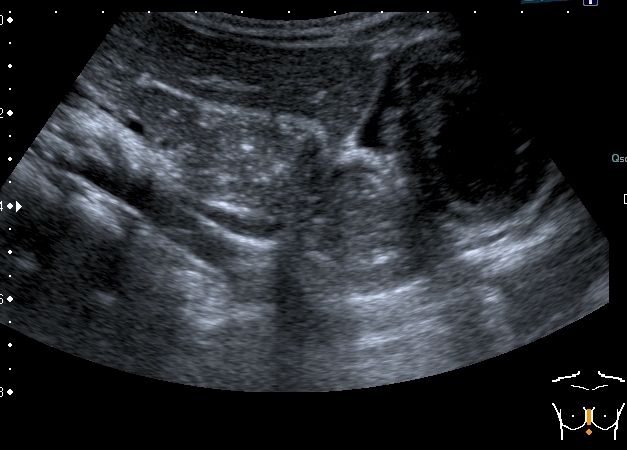

Девочка 4-х лет, жалобы на длительный кашель (оеоло 1-го месяца). В поликлинике выполнена рентгенография органов грудной клетки, выявлены изменения (какие - пока не скажу). Госпитализирована. Направлена на УЗИ сердца. При УЗИ - в самом сердце - патологии не выявлено, но позади него к правому предсердию прилежит полостное образование с акустически неоднородным содержимым.

Сканы через пищеводное отверстие диафрагмы